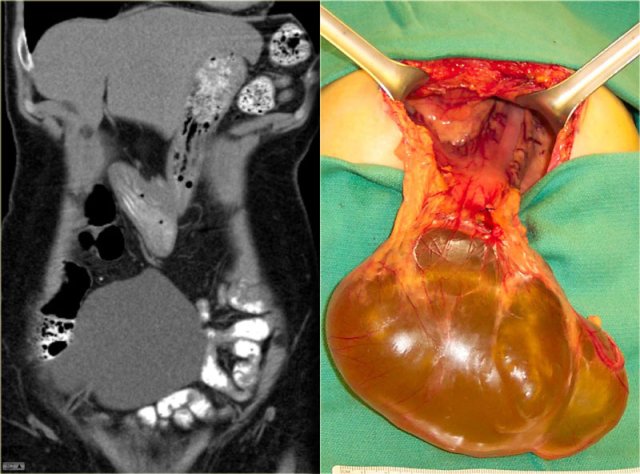

Mesenteric cyst - Lymphangioma

Mesenteric cyst is a descriptive term for any cystic lesion within the mesentery.

Usually it is a lymphangioma.

Other mesenteric cysts like enteric duplication cyst, enteric cyst, nonpancreatic pseudocyst and mesothelial cyst are very uncommon and have no specific features.

Lymphangioma is a benign lesion of vascular origin.

Most lymphangiomas are located in the neck, but 5% of lymphangiomas are abdominal.

Lymphangioma has enhancing septa.

Unlike in cystic peritoneal metastases, ascites is not a feature of lymphangioma.

When you see a septated cystic lesion without ascites the most likely diagnosis is a lymphangioma.

Lymphangioma is often closely associated with the small bowel.

At surgery it is usually very difficult to separate the tumor from the bowel and in many cases the bowel also has to be resected.

The case on the left is also a lymphangioma.

Notice that CT does not always appreciate the septations, although the specimen clearly shows multiple septations.

Ultrasound or MR depict these septations better than CT.